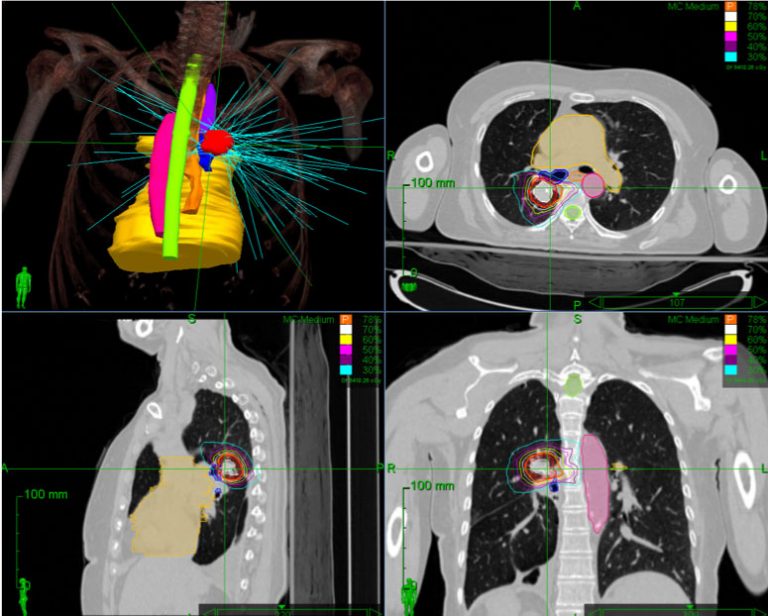

Stereotactic body radiation therapy for nonmetastatic lung cancer: Sbrt is a specialized technique used to treat tumors in the lung, liver and spine while minimizing damage to the surrounding normal, healthy tissues.

Sbrt combines reproducible and accurate anatomic targeting with the delivery of a very high dose per fraction of radiation to a target. The role of stereotactic body radiation therapy for operable patients is expected to be clarified by the outcomes of coming clinical trials. You may be offered sbrt if you have lung cancer that hasn�t spread outside of the lung or if you can�t have or don�t want to have surgery.

Stereotactic body radiation therapy (sbrt) delivers precise, high doses of radiation to a tumor. Listing a study does not mean it has been evaluated by. Radiation is a type of lung cancer treatment designed to only target cancer cells and not affect other parts of the body.

Stereotactic body radiation therapy (sbrt), also known as stereotactic ablative radiotherapy, is a technique of external beam radiation that delivers precisely targeted, ablative doses to extracranial sites. Stereotactic body radiation therapy for inoperable early stage lung cancer. Improvements in imaging and radiation treatment delivery systems however have provided radiation oncologists with new tools to better target these tumors.